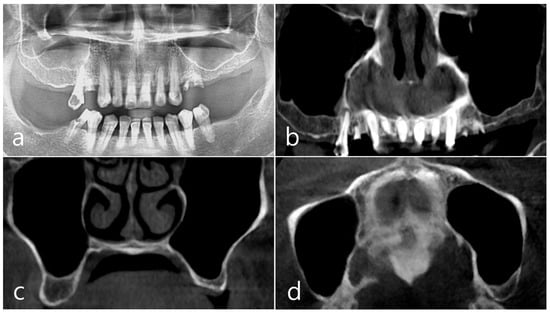

This patient, a 67-year-old female non-smoker, reported no systemic disease that could interfere with the operation. The patient visited the clinic for implant placement for the missing teeth. Panoramic radiography and CBCT were taken. On panoramic radiography, resorption of residual alveolar ridge and pneumatization of the maxillary sinus were observed in the left and right posterior region. Since the amount of residual alveolar bone was 4–6 mm in the maxillary right posterior region, a transcrestal sinus lift was planned (Figure 1a). In the preoperative panoramic, coronal, and axial images of the CBCT scan, abnormal images of the maxillary sinus were not observed, and there was no sinus membrane thickening (Figure 1b–d).

Figure 1. Case 1. (a) In panoramic radiography, resorption of residual alveolar ridge and pneumatization of the maxillary sinus were observed in the left and right maxillary posterior region; (bd) In preoperative CBCT’s panoramic, coronal, and axial images, there were no abnormal findings of the maxillary sinus and no sinus membrane thickening.